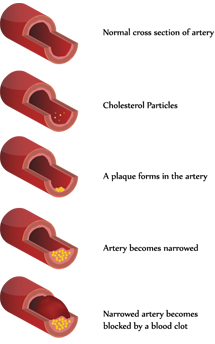

The heart is a muscular organ that pumps blood to the body. Oxygen and nutrients that are required to fuel the pump are carried to the heart in the coronary arteries. The most common cause of coronary artery narrowing is atherosclerosis where fatty deposits (plaques) build up within the coronary arteries.

As the arteries become narrowed, blood flow to the heart may be reduced during times of increased need (exercise, emotional stress). The imbalance between the supply and demand of oxygen can cause central chest discomfort. This pain can also radiate into the jaw and down the arms and be associated with breathlessness, nausea and sweating. This is known as angina. When the blockage is severe enough to completely cut off the supply of oxygen to the heart muscle, a heart attack can result.

In other cases, plaques within artery may develop a slight crack which stimulates the production of blood clots that try to seal off the crack. The clot also gets into the crack and causes it to rise and further obstruct the middle of the artery. The sudden increase in the obstruction caused by the raised ruptured plaque and associated clot can transform a mild blockage into a critical one within a matter of hours. The decrease in blood flow to the heart muscle is severely reduced and the patient begins to have severe and prolonged chest pain that occurs at rest and may even awaken him or her from sleep. This is known as unstable angina.

However, the clot may continue to grow which can completely block the artery and cut off blood flow to the part of the heart muscle that it supplies. Without oxygen and nutrients, the patient suffers a heart attack and the involved heart muscle can get permanently damaged. There are several forms of treatment that can restore blood flow to the artery but this needs to be carried out at as an emergency in hospital.